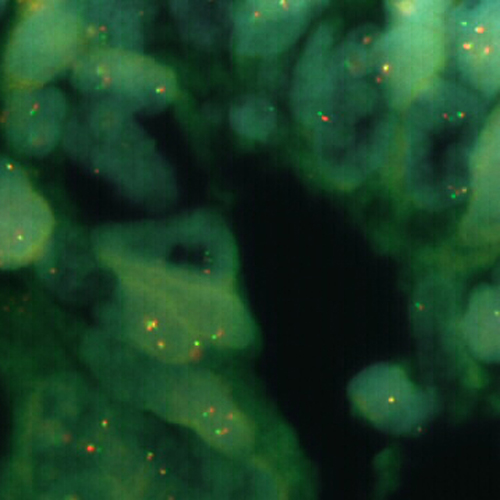

FUS (16p11) Break probe hybridized to liposarcoma material.

The fused in sarcoma (FUS) gene was originally shown to be rearranged in myxoid liposarcomas harboring a t(12;16)(q13;p11) translocation. FUS has also been shown to be involved in other recombinations: with ERG in acute myeloid leukemia carrying a t(16;21), with ATF1 in band 12q13 in angiomatoid fibrous histiocytoma, and with CREB3L2 in fibromyxoid sarcoma. A break or split probe for FUS is best used to analyze translocation of the FUS (16p11) gene on formalin fixed paraffin embedded tissue for routine clinical diagnosis. The FUS (16p11) Break probe is optimized to detect translocations involving the FUS gene region at 16p11 in a dual-color, split assay on metaphase/interphase spreads and paraffin embedded tissue sections.